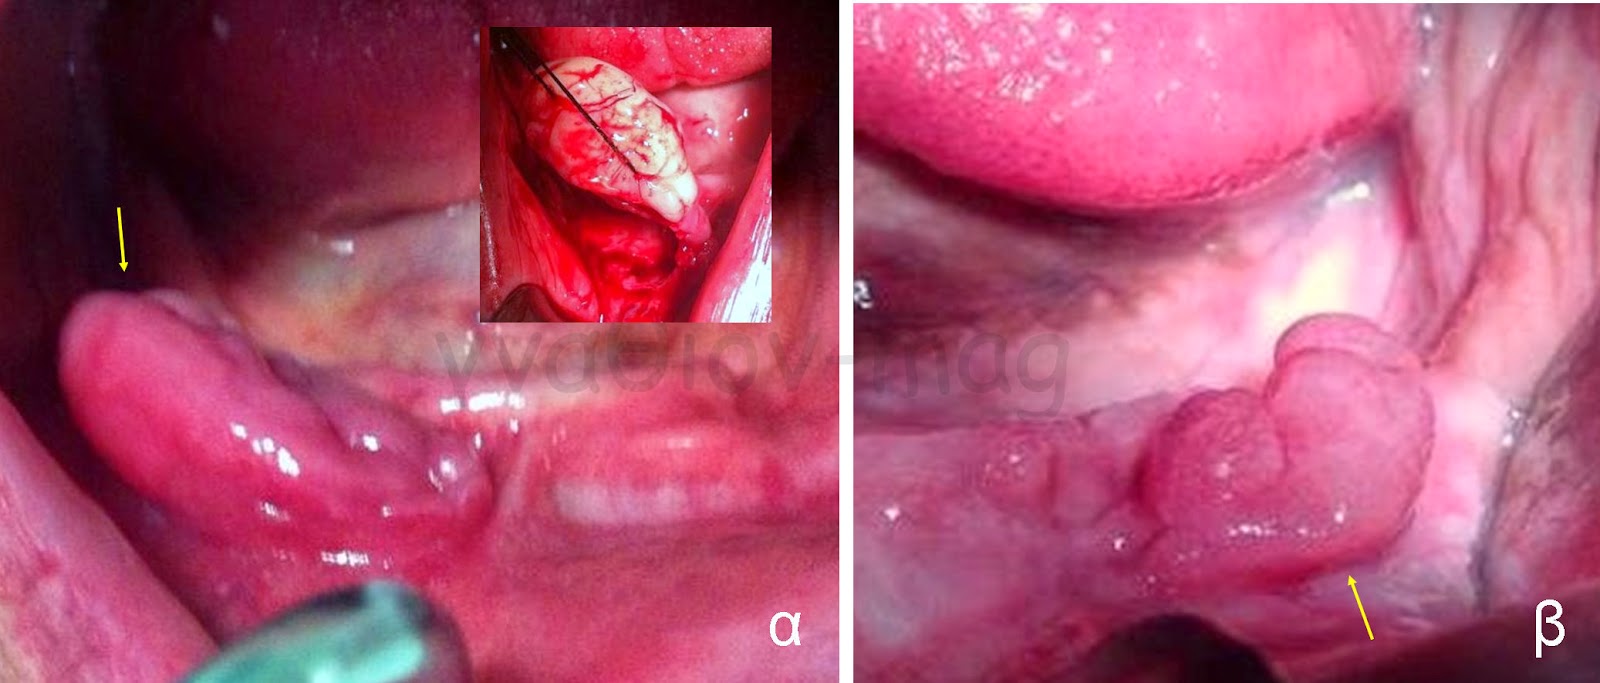

Οι πιο συχνές βλάβες στο στόμα είναι τα αποστήματα, τα οποία όταν οφείλονται σε μικροβιακές λοιμώξεις δοντιών της άνω γνάθου μπορούν να εκδηλώνονται και στην υπερώα (Εικόνα 3). Η θεραπεία τους προϋποθέτει την θεραπεία του υπεύθυνου δοντιού.

Εικόνα 3. α. Απόστημα που οφείλεται σε γομφίο οδόντα (βέλος), β. Απόστημα που οφείλεται σε τομέα οδόντα (βέλος).